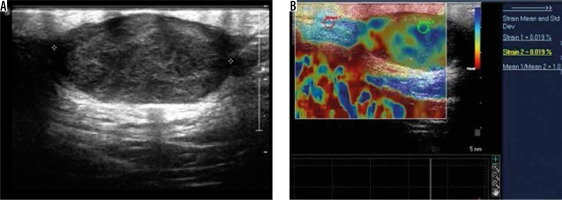

Epidermoid cyst – greyscale ultrasound image (A) shows a well-defined, predominantly hypoechoic lesion with posterior acoustic enhancement. Strain elastography assessment (B) of the same lesion depicts it predominantly in blue colour on elastography map and a strain ratio of 1.03 suggesting the “soft” nature of the lesion and a pointer towards a benign aetiology

These results in the context of epidermoid cysts in the present study are also comparable to the study of superficial soft tissue masses by Hung et al. [9]. The “pseudotestis” appearance of epidermoid cysts was extensively studied by Huang et al. in a retrospective study of 42 surgically proven cases [12]. The pseudotestis appearance is characterised by an ovoid nodule with homogeneous echoes within.

The mean strain ratio in epidermoid cysts was 1.19 ± 0.08, which overlapped with that of lipomas (1.34 ± 0.45). The retrospective study by Park et al. found no significant differences between the strain elastography scores of epidermoid cysts and that of other benign tumours [13]. However, the epidermoid cysts were softer than the malignant superficial tumours. Although our study had limited number of cases, the single subcutaneous metastatic lesion we encountered had a strain ratio of 3.2 and that of fibroma and neurofibroma was higher than that of epidermoid cyst at 2.15 ± 0.92 and 2.85 ± 0.54, respectively. However, the significance of this could not be ascertained because it was a single case.